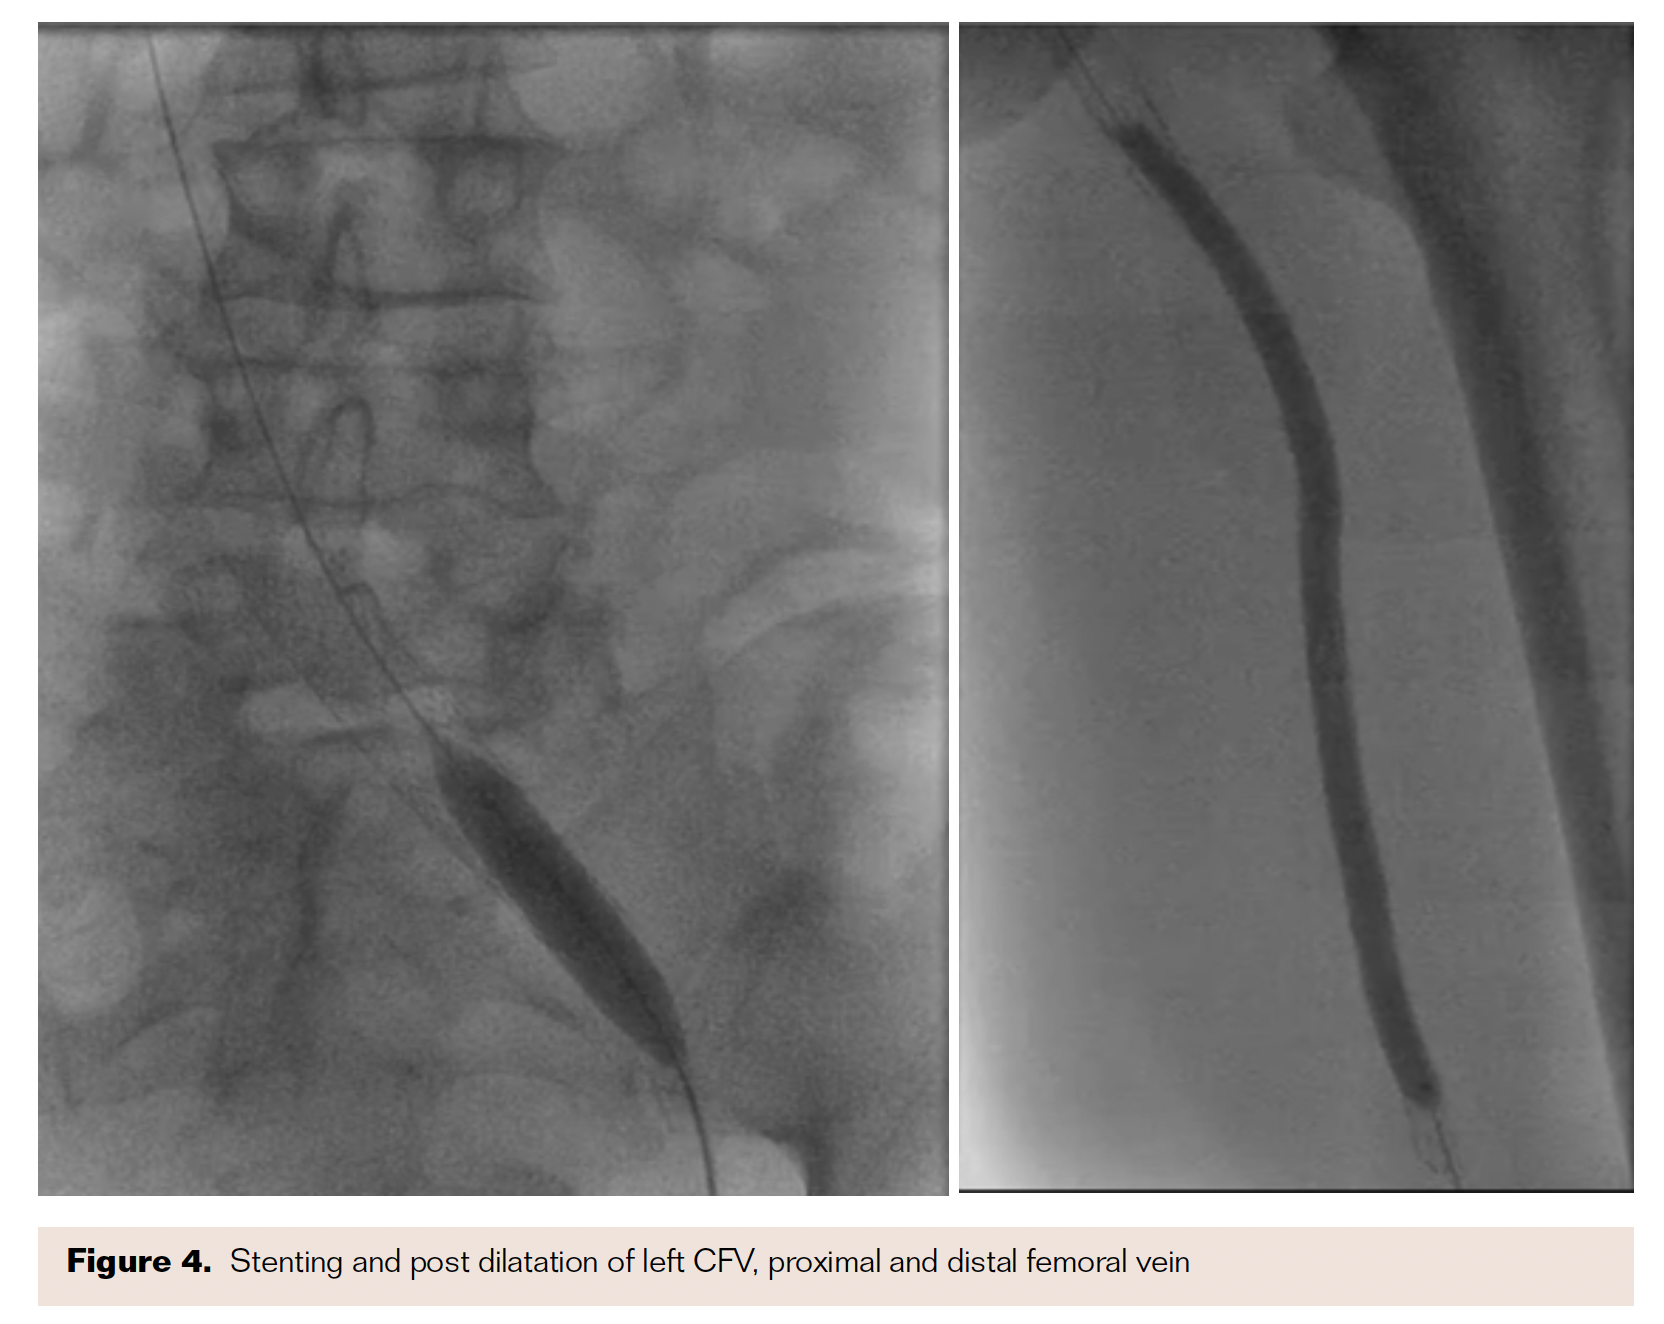

The presentation was consistent with PTS, despite being compliant with warfarin therapy and therapeutic INR. Venous duplex of bilateral lower extremities revealed occlusive thrombus in the left common femoral vein (CFV), near-total occlusion of left superficial femoral (SFV), and popliteal vein with thickening of greater saphenous vein (Figure 1). The patient was then referred for venography of left lower-extremity for further assessment and definitive therapy.